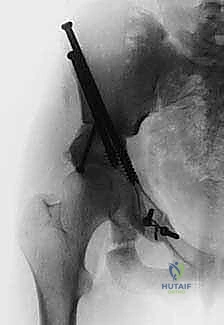

باستخدام أدوات خاصة، يقوم الدكتور هطيف بتدوير التجويف الحقي الحر في ثلاثة أبعاد (للأمام، وللخارج، وللأسفل) حتى يغطي رأس عظم الفخذ بشكل مثالي وميكانيكي سليم. يتم التحقق من الزاوية الجديدة فوراً داخل غرفة العمليات باستخدام جهاز الأشعة السينية المتحرك (C-arm).

5. التثبيت القوي (Fixation)

بمجرد الوصول إلى الوضع المثالي، يتم تثبيت العظام في مكانها الجديد باستخدام براغي معدنية قوية من التيتانيوم أو دبابيس (K-wires). هذا التثبيت يضمن التحام العظام بشكل صحيح خلال فترة التعافي.